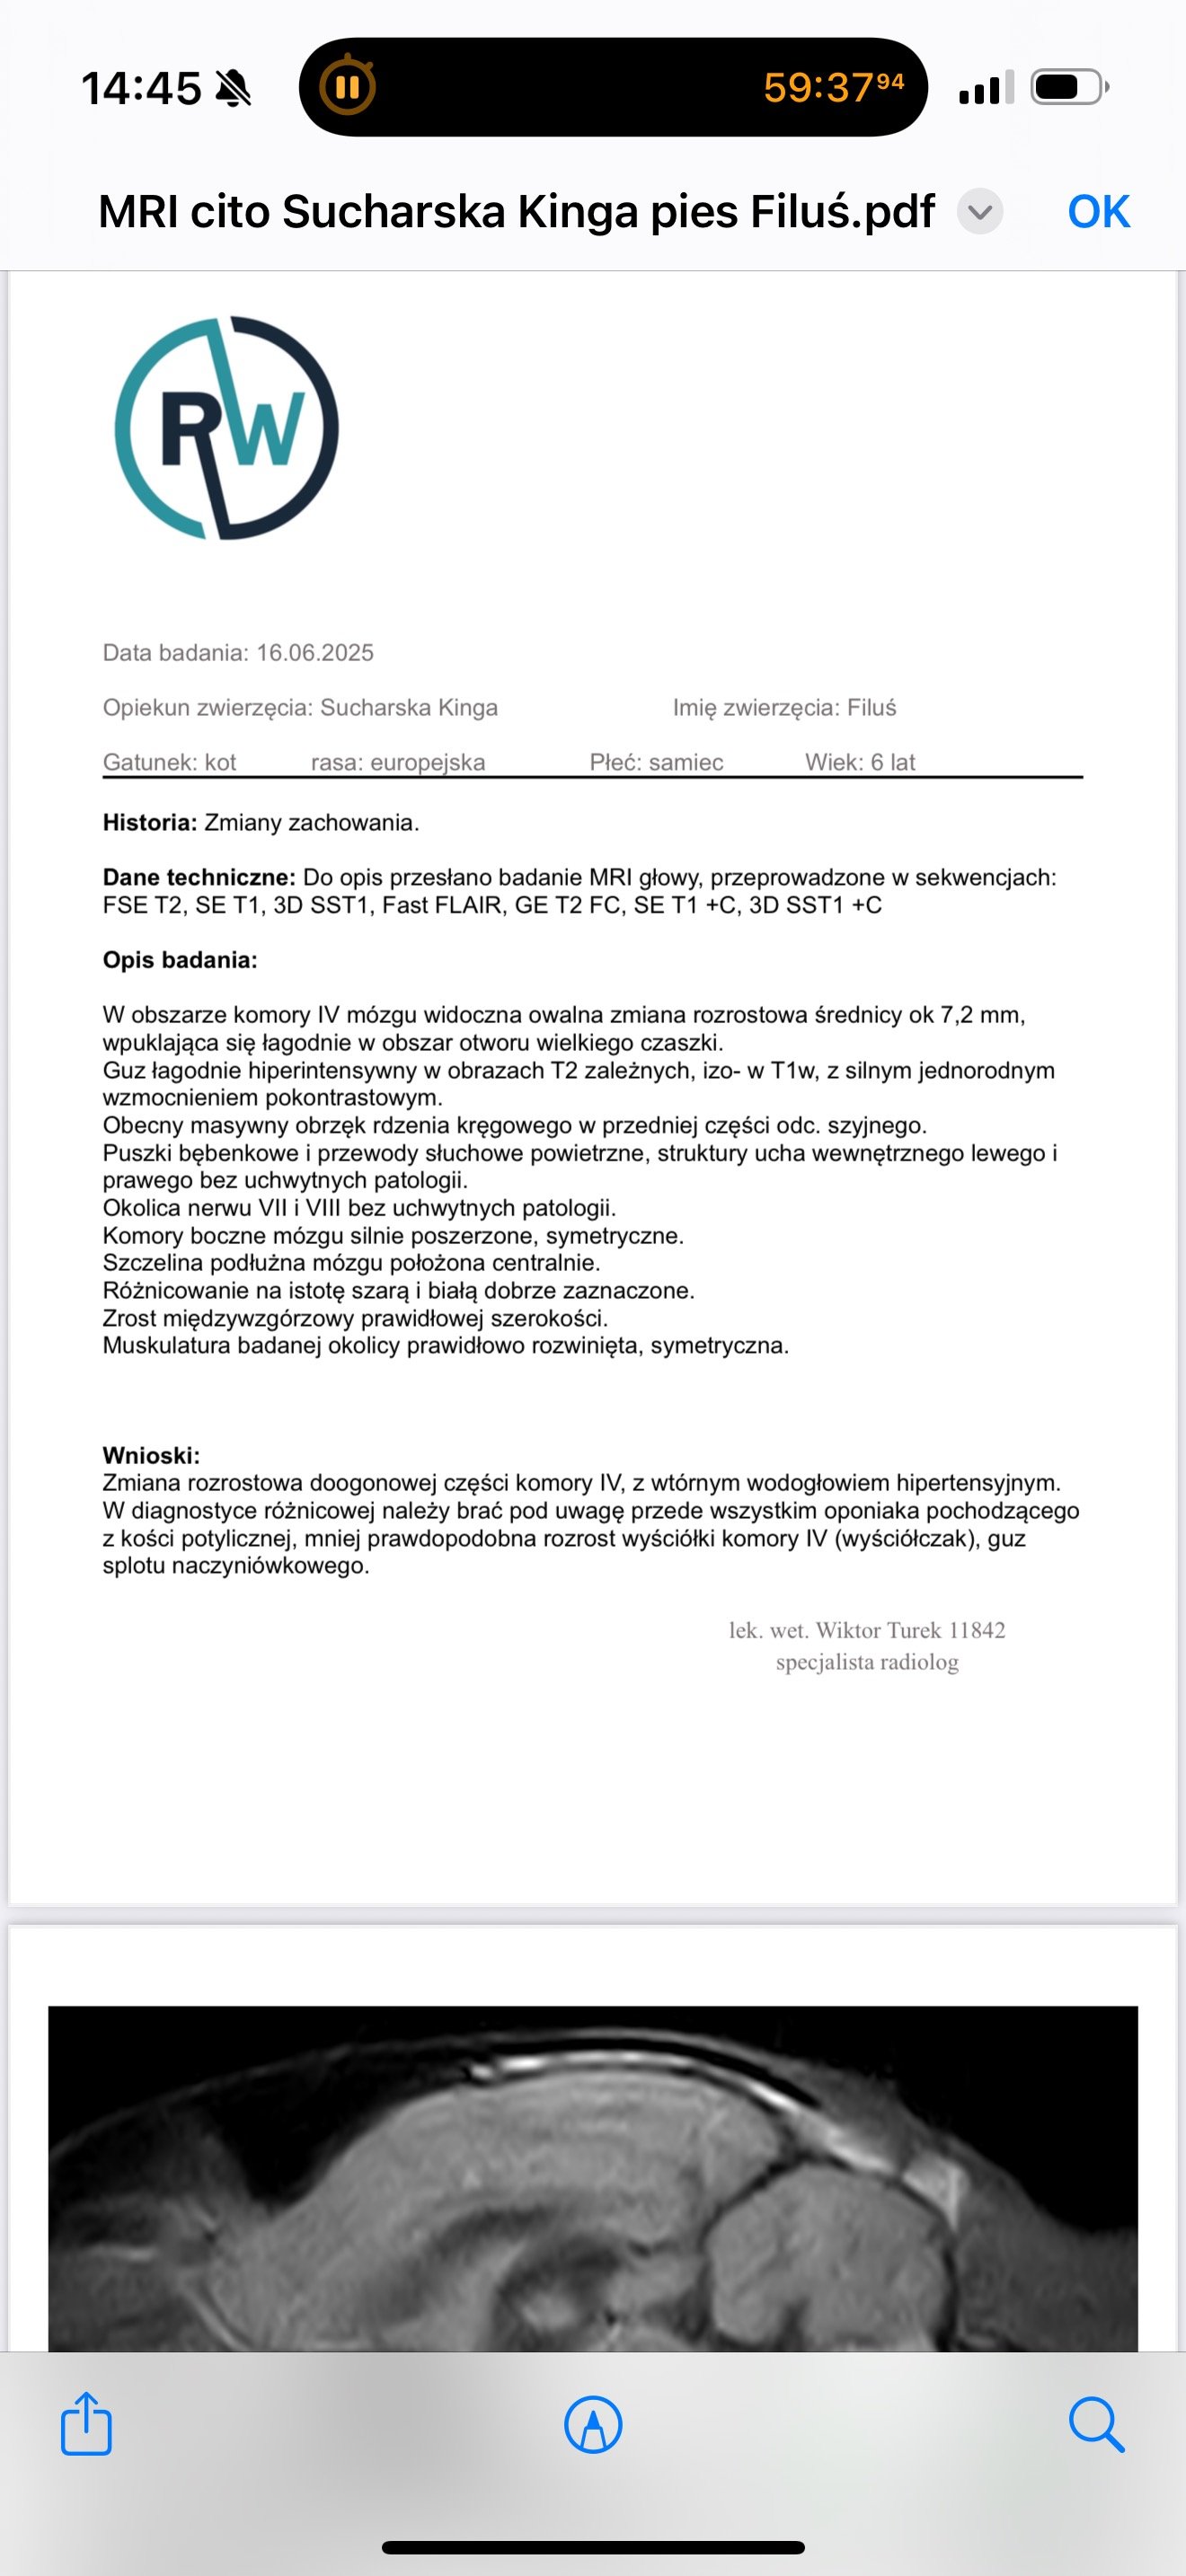

16.06.25 wykonaliśmy rezonans w Poznaniu w klinice Wąsiatycz, który wykazał nam zmianę w postaci oponiaka, niestety bez pobrania płynu ze względu na jego duży nadmiar, a doktor wskazał to jako przeciwwskazanie do wykonania tego zabiegu.

23.06.25 Udaliśmy się z polecenia na wizytę konsultacyjną do kliniki NeuroTeam we Wrocławiu, gdzie dostaliśmy wstępnie zielone światło na wykonanie operacji. Tylko dzięki temu będziemy w stanie uratować mojego Filusia i dać mu szansę na dalsze życie z dala od bólu i cierpienia. Jest ze mną od miesięcznego malucha i nie wyobrażam sobie, aby choroba taka jak ta mi go zabrała, jest moim synkiem. Rokowania bez operacji są bardzo niskie, ze względu na jego dotychczasowe samopoczucie, utrzymujące się wymioty (rzadziej ale jednak nadal występują - w postaci samej wody lub śliny), wagę (2kg) oraz jelita, które słabo pracują pomimo codziennych leków.